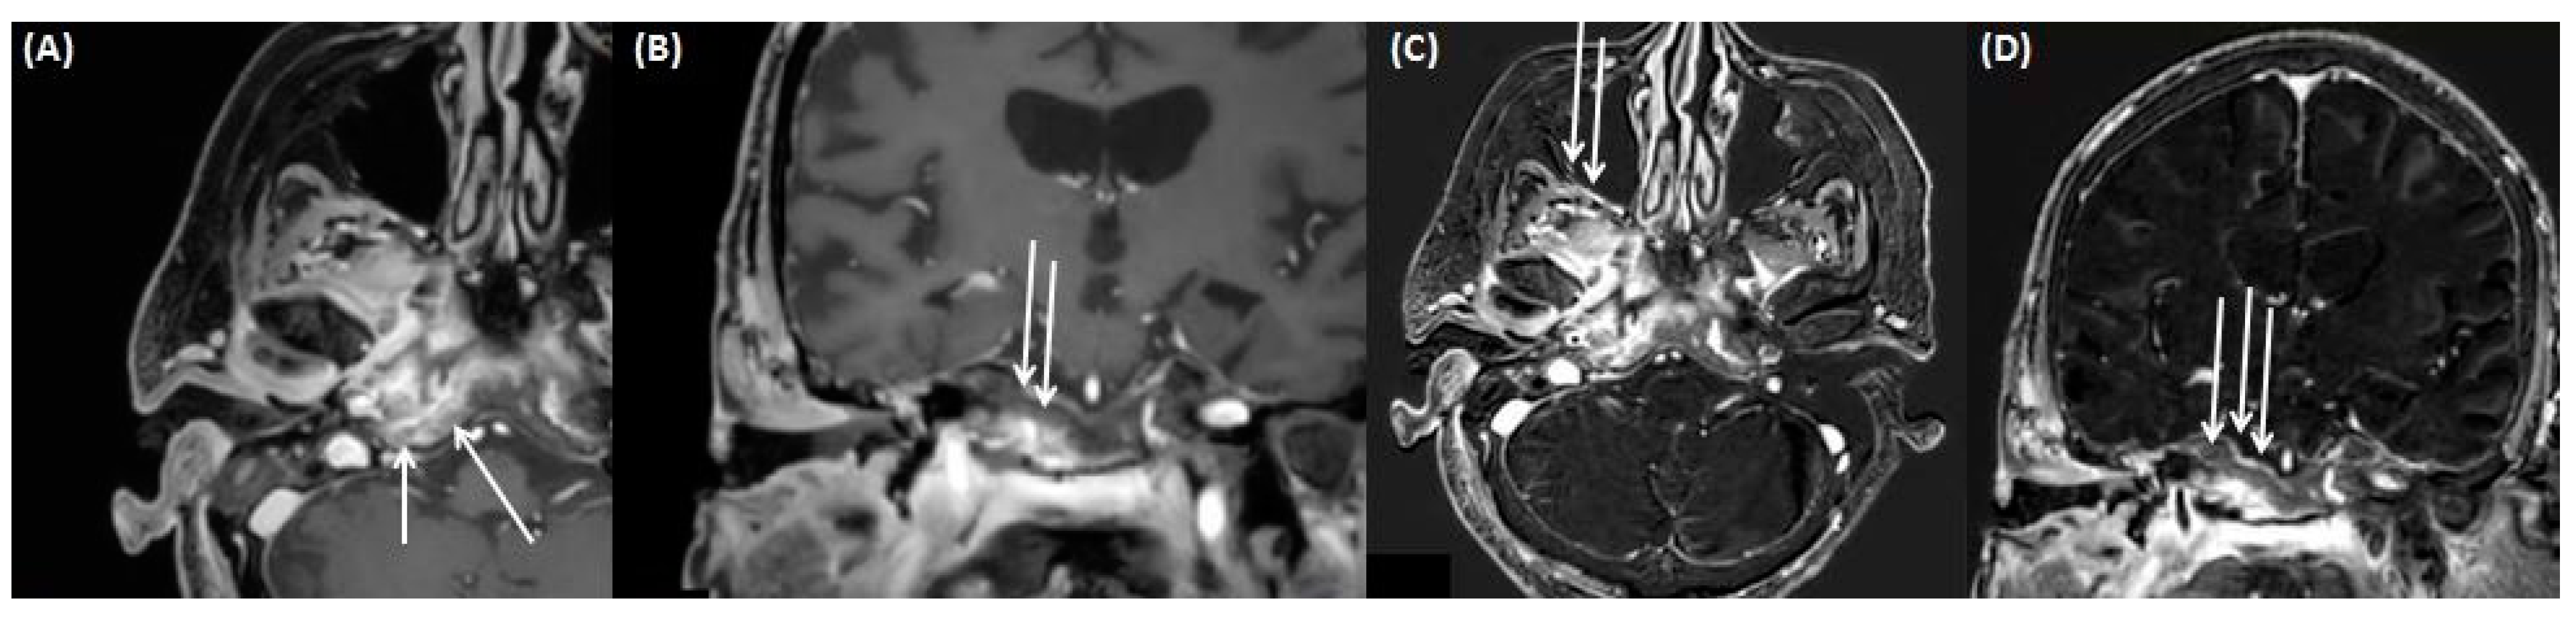

4.1. Gradenigo’s Syndrome

4.2. Intracerebral Abscess/Emphysema/Meningitis